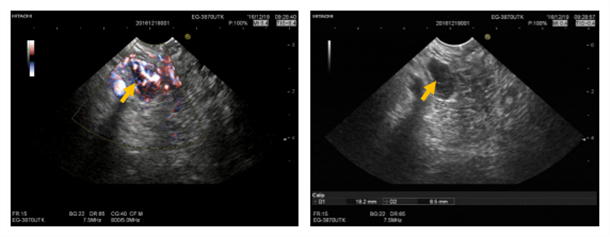

首次超声内镜检查:病变位于胰头近钩突位置,截面椭圆形血供丰富。